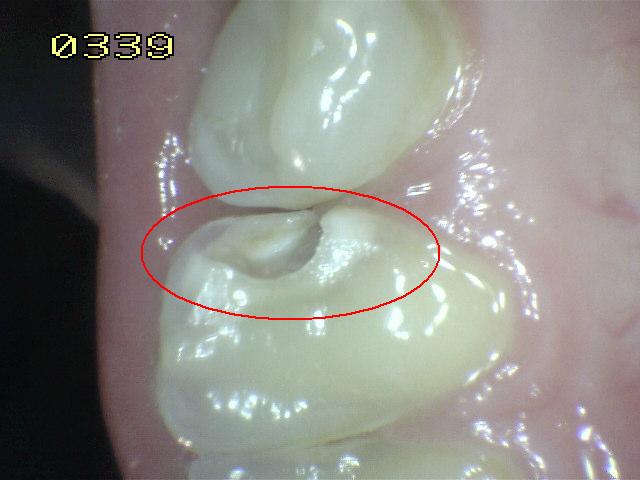

Código 5

(Caries Severa): Cavidad

detectable con dentina visible hasta la mitad de la superficie. |